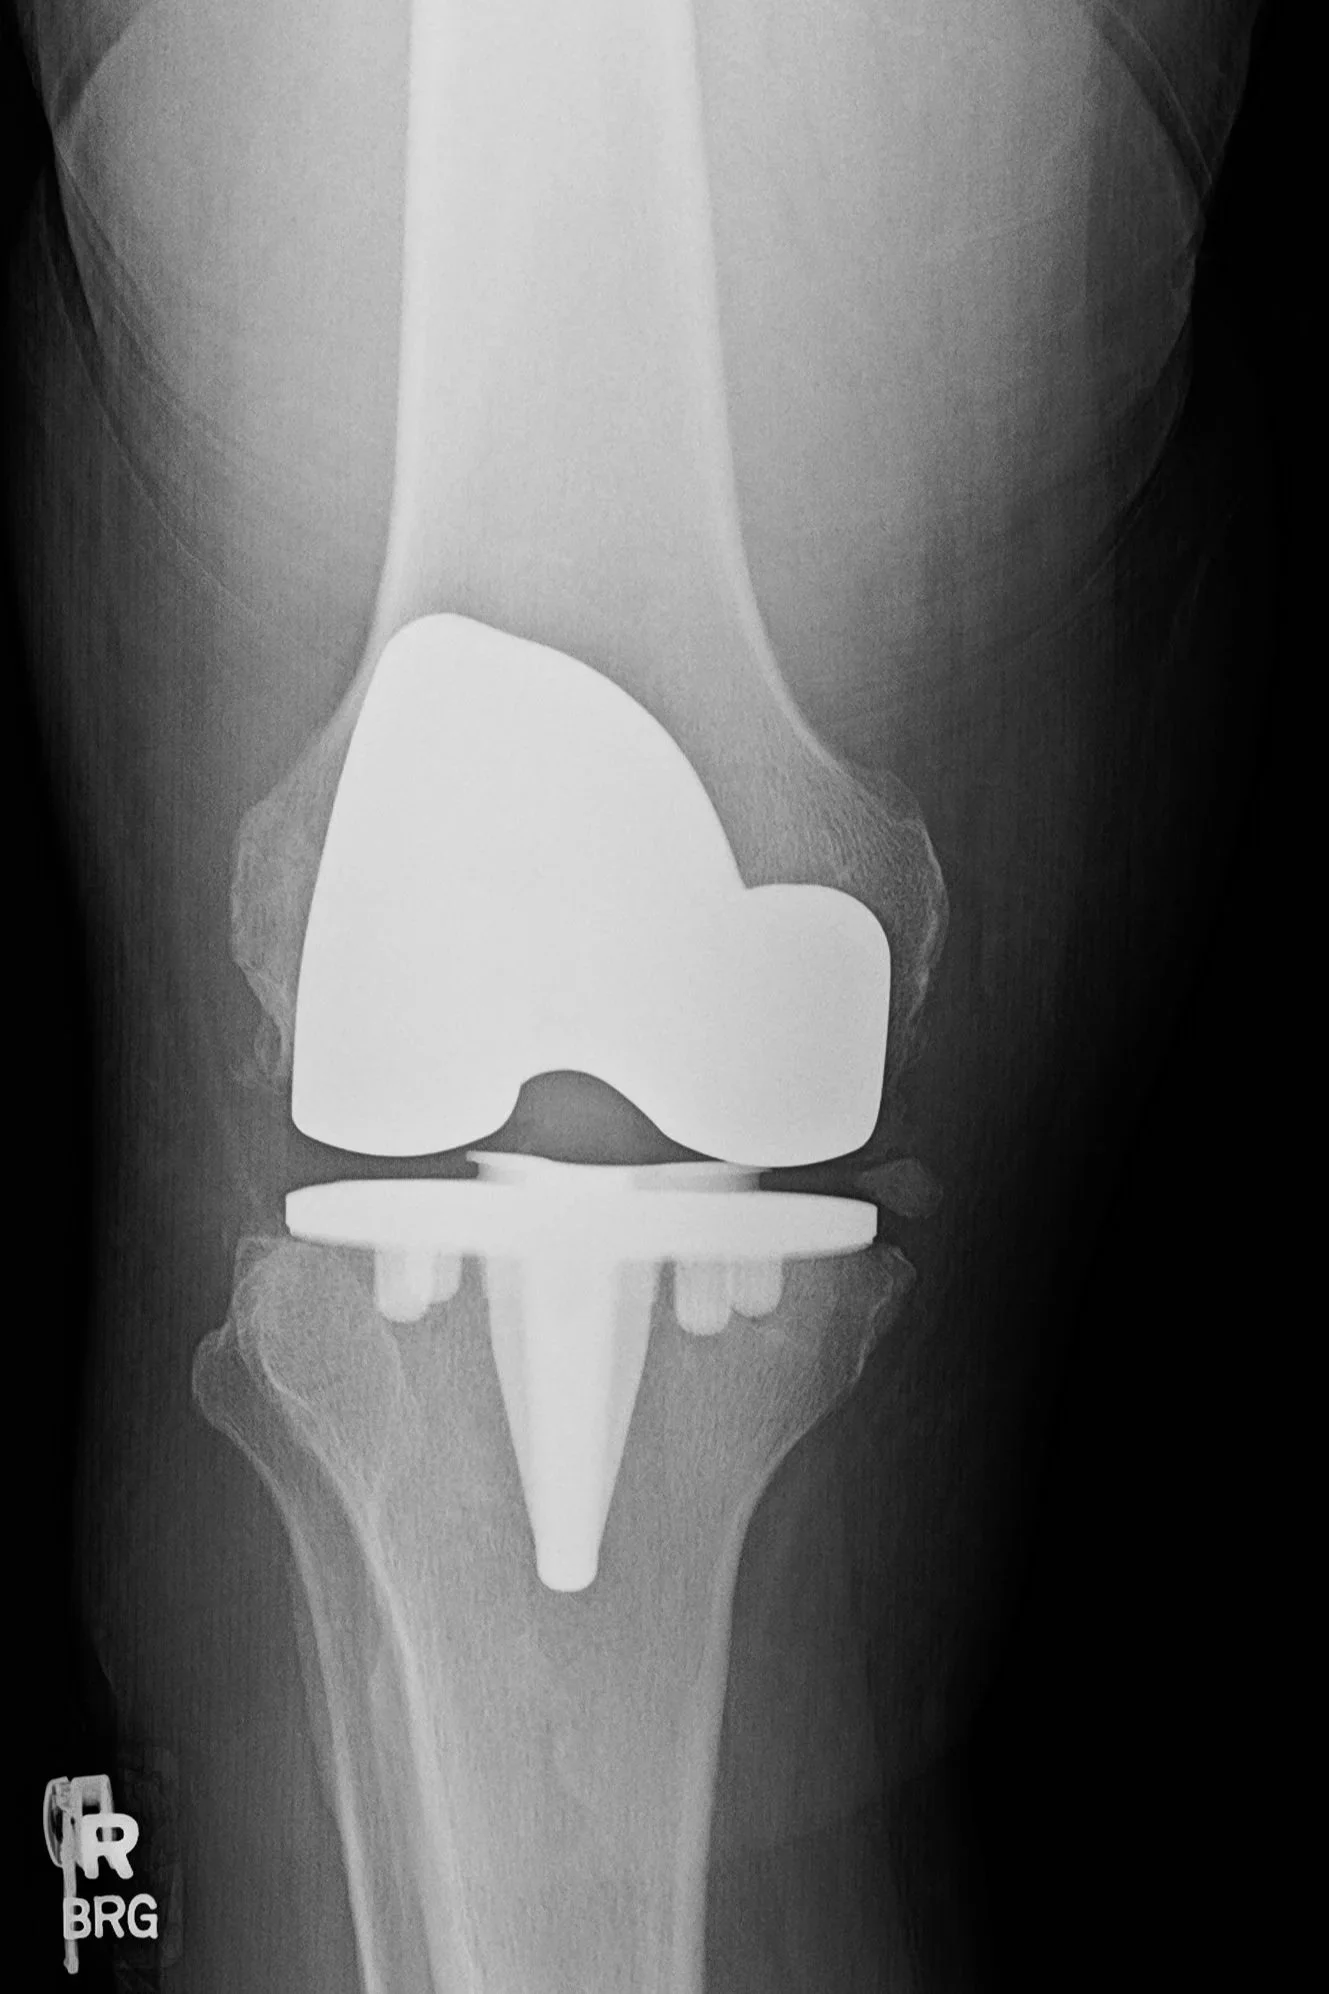

X-ray showing total knee replacement with prosthetic components in place.

After

Total knee replacement restores alignment and creates a smooth surface for pain-free activity.